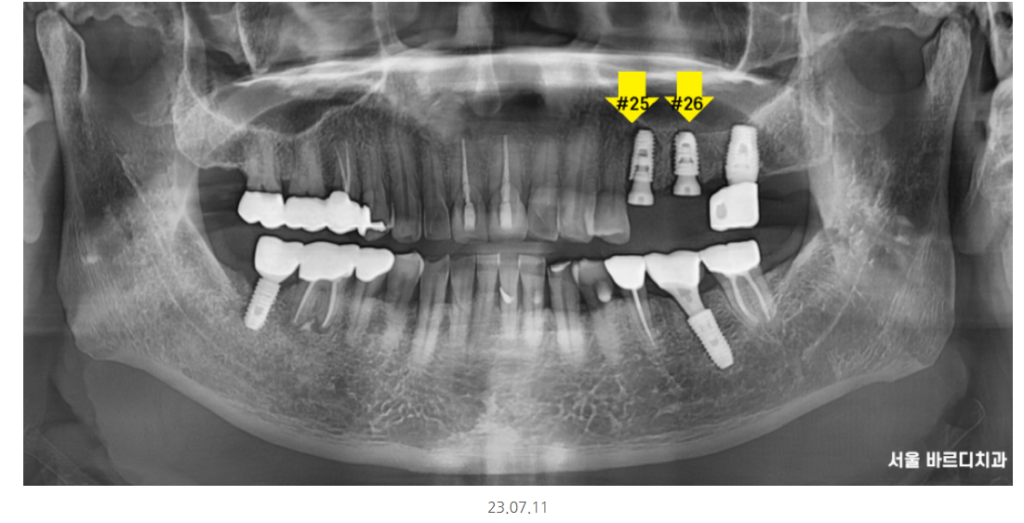

파노라마 전체 사진상으로도

좋아 보이지 않아

자세히 관찰할 수 있는

작은 x-ray를 한 장 더 찍어 보았습니다.

노랗게 동그라미 친 부분이

치아 뿌리 끝에 염증을 의미합니다.

이미 치료를 받은 치아에 염증이 생겨

주변 뼈를 녹이고 있는 상태

옆에 치아도 좋지 않은 것은 마찬가지였습니다.

x-ray를 찍었습니다.

남아있는 치아 뿌리는 없는지?

눈으로 1차 확인하였지만

한 번 더 안전한 과정을 거친 후 수술을 진행

발치 후 당일 임플란트 식립 후 사진입니다.